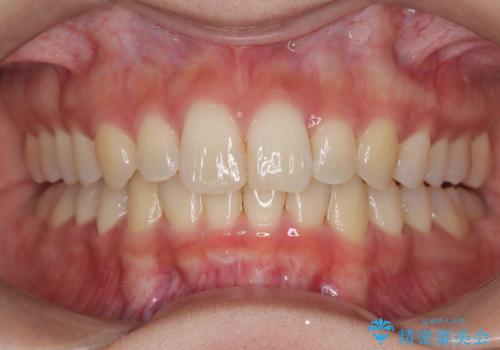

ディープバイト改善のためのインビザライン治療

- 患者様は、全体的な歯列のガタガタとディープバイト(深い噛み合わせ)を主訴として来院されました。診断の結果、ディープバイトを改善するためには、歯列全体の拡大が必要であると判断しました。治療には、透明なマウスピース型矯正装置「インビザライン」を使用し、歯を適切に拡大しながら歯並びを整える計画を立てました。治療期間はおおよそ2年を見込んで進め、最終的に見た目にも大きく変化をもたらすことを目指しました。

ディープバイトの治療には、奥歯の高さや前歯の位置に対する繊細な調整が必要です。本症例では、インビザラインによる歯列拡大を行うことで、噛み合わせを改善し、歯並び全体を整えました。治療過程では、歯間のスペースを確保するため、IPR(インタープロキシマルリダクション)を適宜行い、無理なく歯列の調整を行いました。治療後は、歯並びが大きく改善され、患者様の見た目にも大きな変化が現れました。インビザラインは透明で目立たず、治療中の見た目を気にされる患者様にも配慮した治療法です。